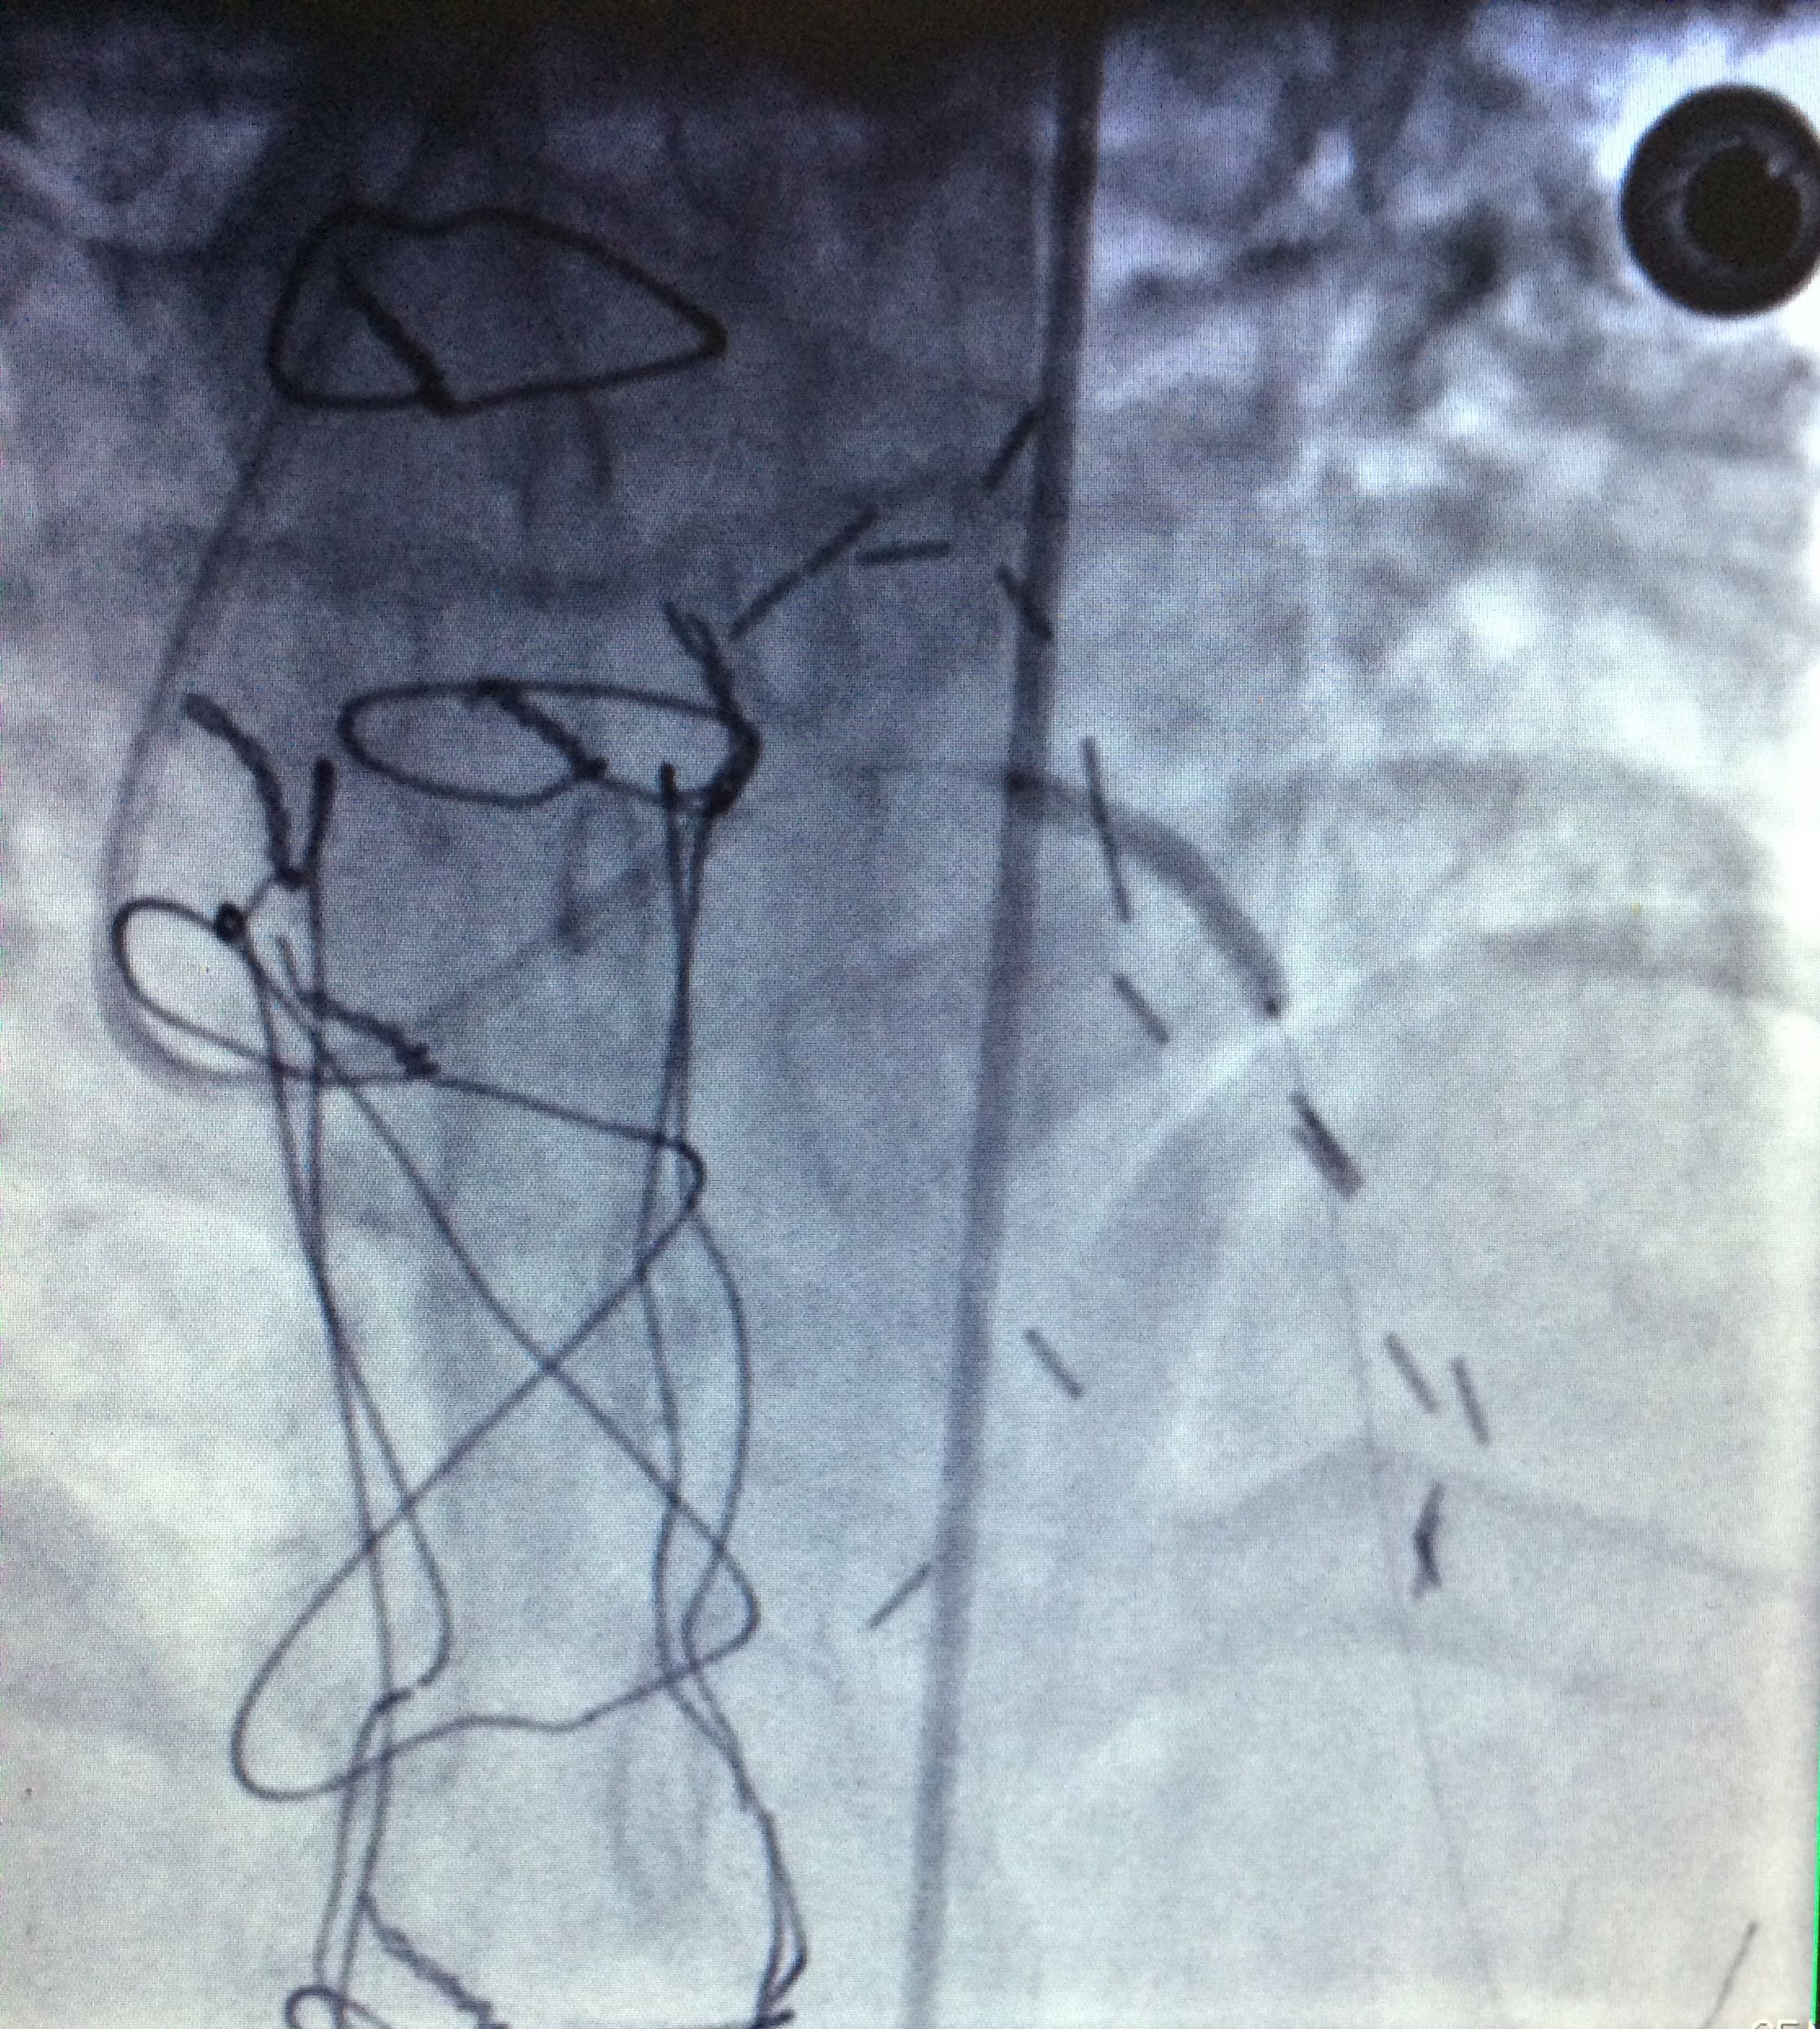

5. Right coronary artery with total occlusion at the proximal third (Figure 1-3).

Figure 1 Right coronary artery with total occlusion at the proximal third.

Figure 2 Right coronary artery with total occlusion at the proximal third.